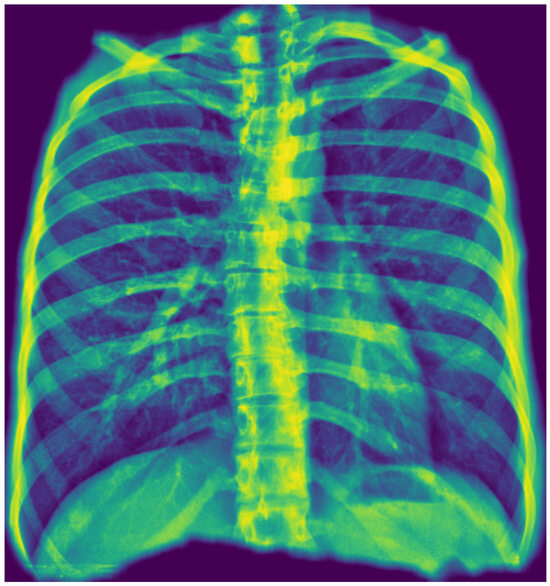

To enhance model transparency and validate spatial reasoning, we applied Gradient-weighted Class Activation Mapping (Grad-CAM) to visualize the regions most influential in classification decisions. Grad-CAM served a dual purpose in this context: first, it verified that the model’s predictions are based on clinically relevant regions within the segmented thoracic area; second, it contributed to interpretability by generating intuitive heatmaps that highlight the anatomical structures driving the model’s output. This step was crucial for improving classification accuracy and verifying that it relied on the correct visual cues, aligning with radiological expectations. For optimization, they were only generated when the classification probability score was above the defined threshold.

Representative Grad-CAM overlays are shown in Figure 3, Figure 4, Figure 5 and Figure 6, illustrating several different types of pathologies. These visualizations demonstrate where the algorithm focuses attention on the appropriate pathological regions, thereby reinforcing the validity and interpretability of the proposed pipeline.

Figure 3. Example of Grad-CAM visualizations localizing detected findings. The figure shows the original image (top left) alongside three types of explanatory outputs generated by the algorithm: a heatmap (top right), a contour outline (bottom left), and a bounding box (bottom right). All visualizations are derived from the same process, showcasing different output options.